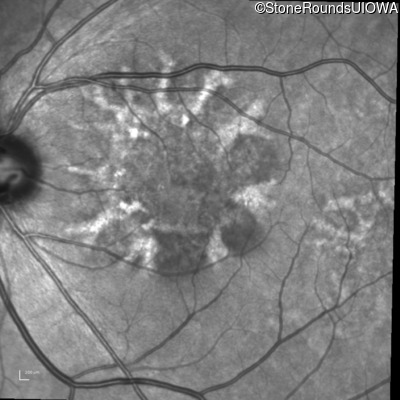

Blue Autofluorescence - Left - 20/20

Exemplar